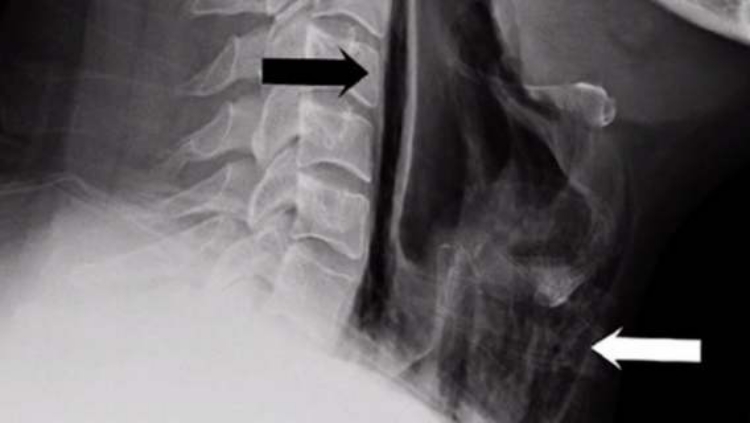

This unusual case was also described in the British medical journal BMJ Case Reports. It was found that this young man had been suppressing sneezes essentially his whole life, simply because he felt sneezing in public was improper. It took a while to discover this bizarre cause of his troubles. First, by palpation (touch) the doctors found that the soft tissues of his neck were significantly damaged. Odd sounds were also heard on auscultation, some cracking and popping. The cause then became clear from the X-ray. Air bubbles had entered the soft tissues of his neck. It therefore likely resulted from a perforation of the soft tissue of the neck due to excessive pressure while suppressing a sneeze, and air got where it shouldn’t. A widespread emphysema was found in the front of the neck, i.e., air bubbles in the soft tissue and subcutaneous tissue.